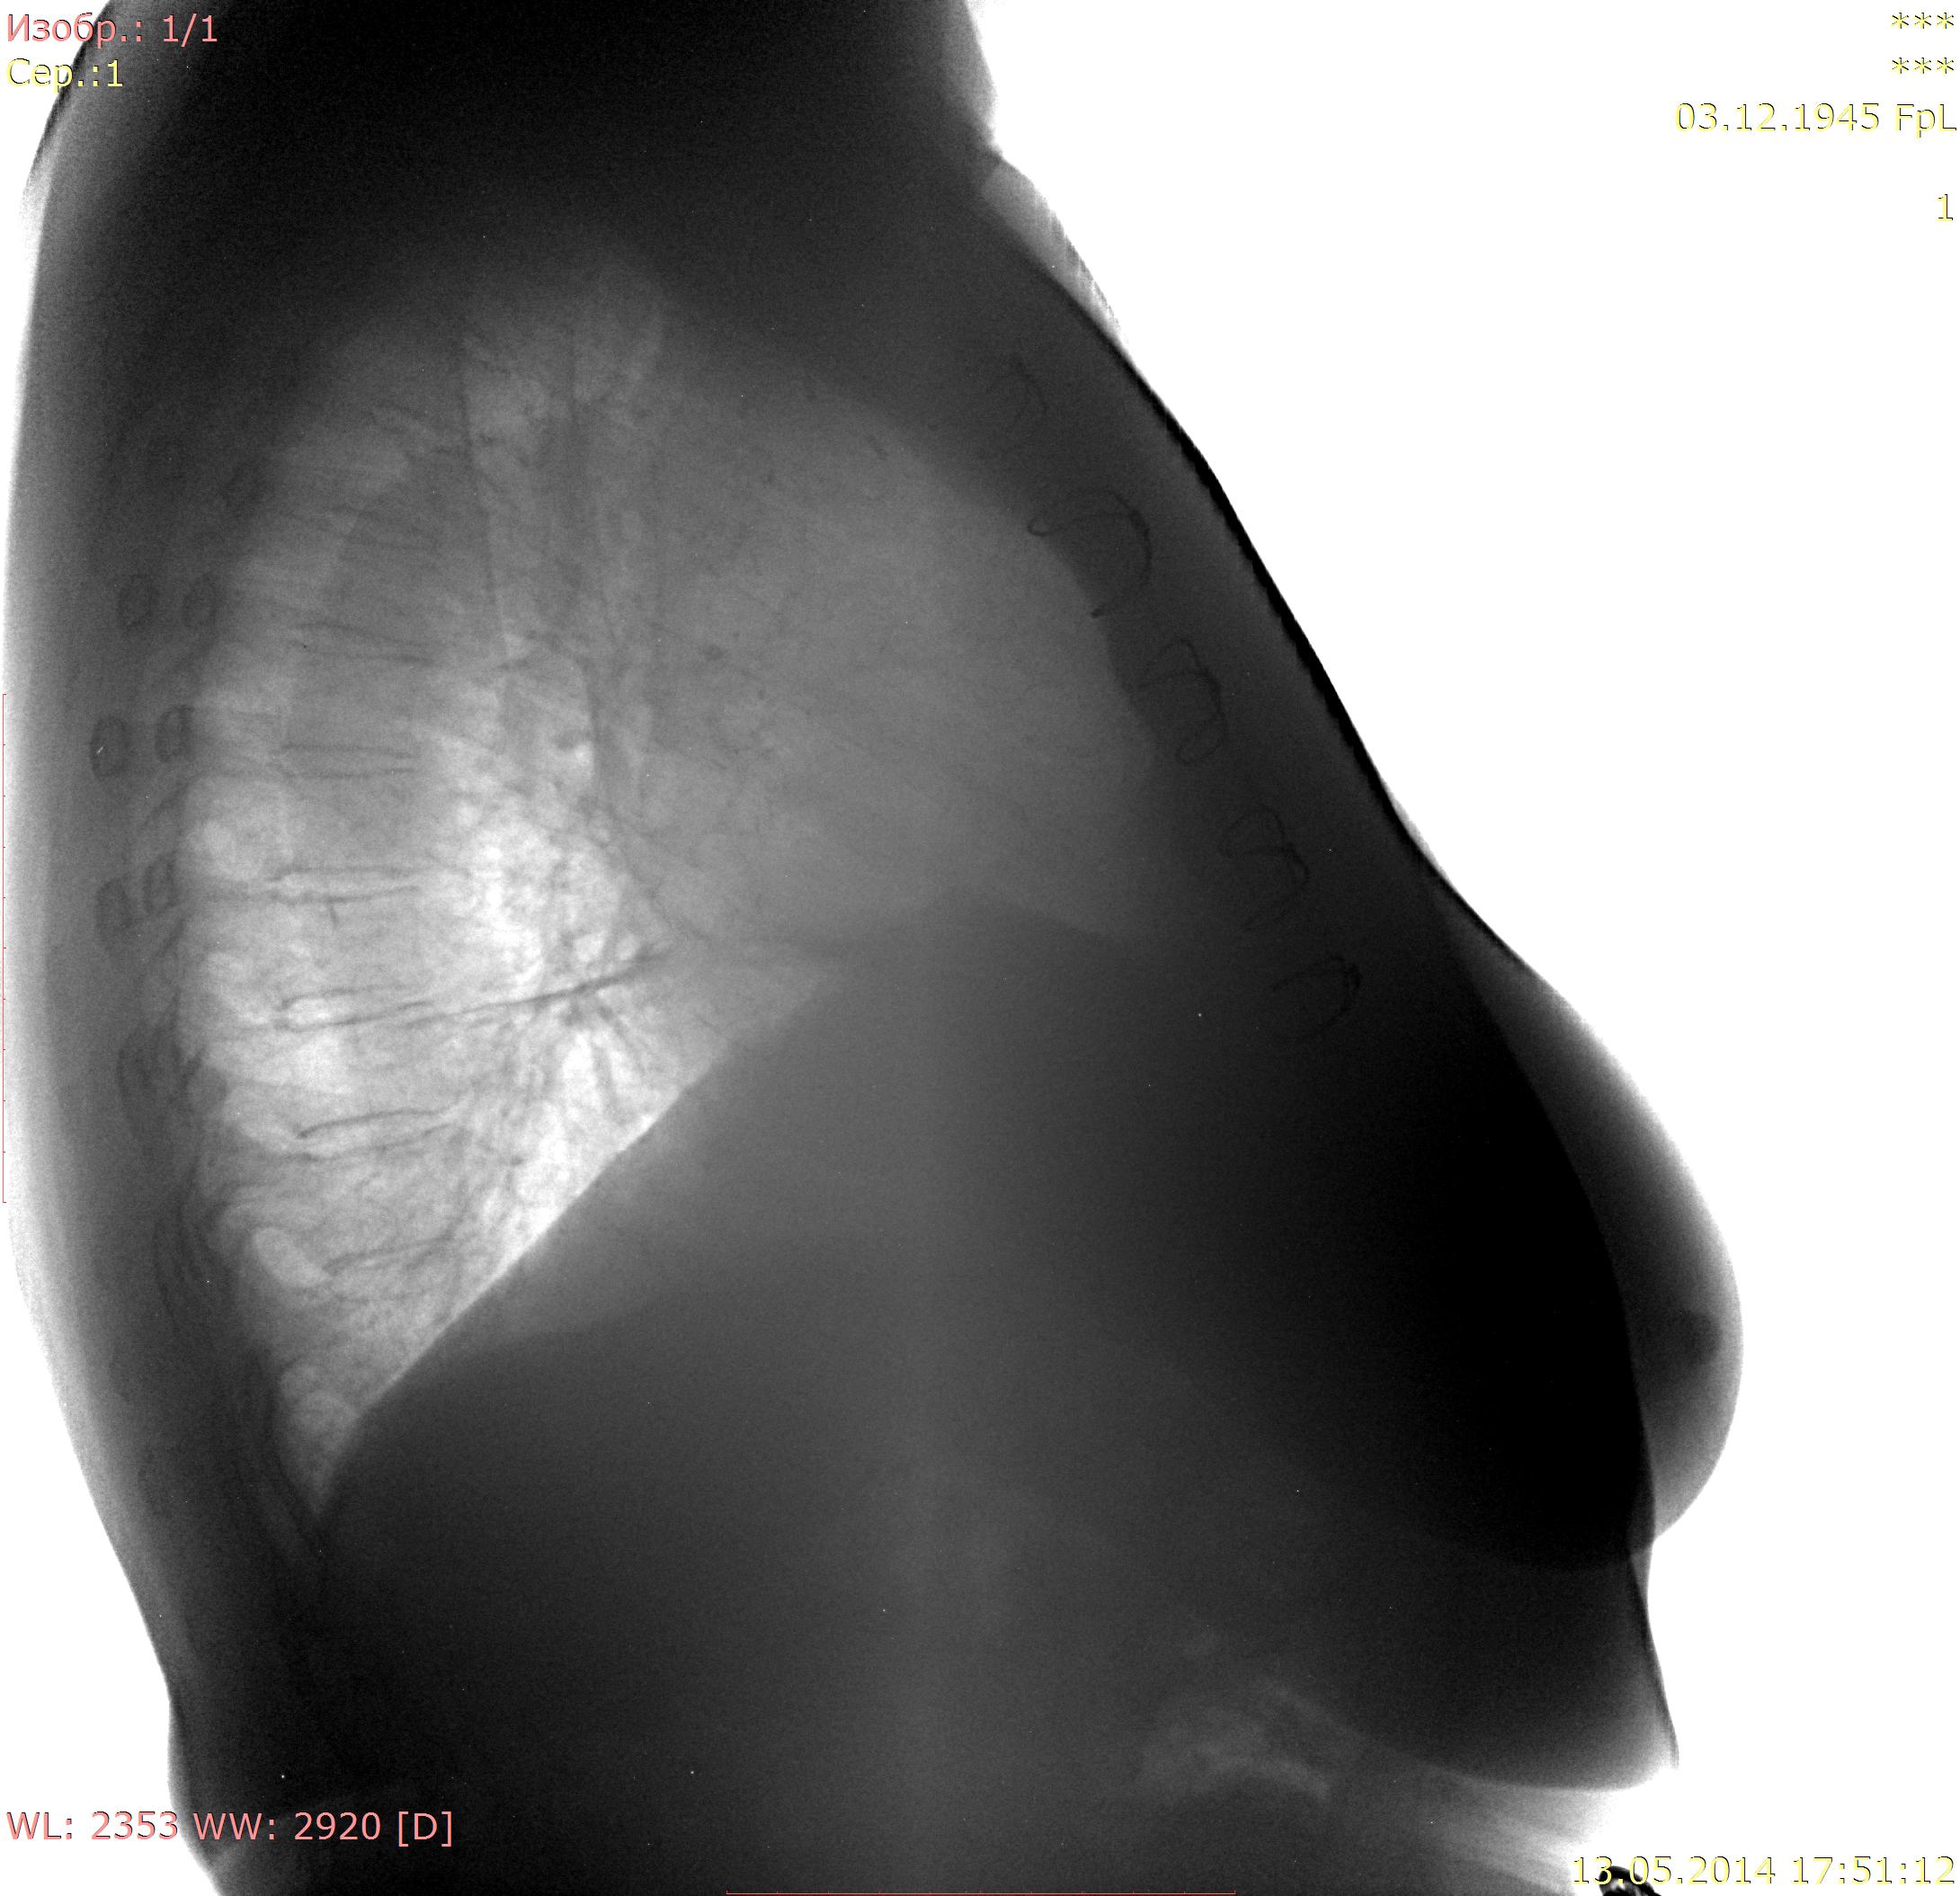

Пациентка 1945 г.р. Флг для ВТЭК, жалоб особых нет, температура нормальная, дыхание свободное. Архив от 2010 - без особенностей. В начале апреля 2014 г АКШ, согласно выписке R перед операцией - без особенностей, после операции - отмечалось высокое стояние пр купола диафрагмы. Самих снимков нет. Дисковидный ателектаз в S9 справа, тень с четкой верхней границей (в медиальных её отделах) над диафрагмой на прямом - признаки гиповентиляции? Или тень - плевральные наложения? Требуется ли контроль\дообследование?

Состояние после стернотомии.Линейная тяжистость в нижней доле справа( фиброз). Релаксация правого купола диафрагмы.( Дообследование не требуется).

Я считаю, плевродиафрагмальной швартой ( гляньте на боковой. Или стрелку рисовать?)

ХЗ, скиалогия какая-то, может организовавшаяся жидкость в междолевой щели.

NIL wrote:

Вы про №1?

А меня смущает тень №2 - по-моему, это не очень похоже на фиброз.

Это вполне может оказаться жидкость с заходом в нижние отделы главной м/долевой щели, уже осумкованная,и в малом количестве. Базальные сегменты поджаты( дисков. ателектаз) -горизонт. тень. Со временем все рассосется.Но купол останется высоким, если не "раздышится".При R-контроле все увидите.